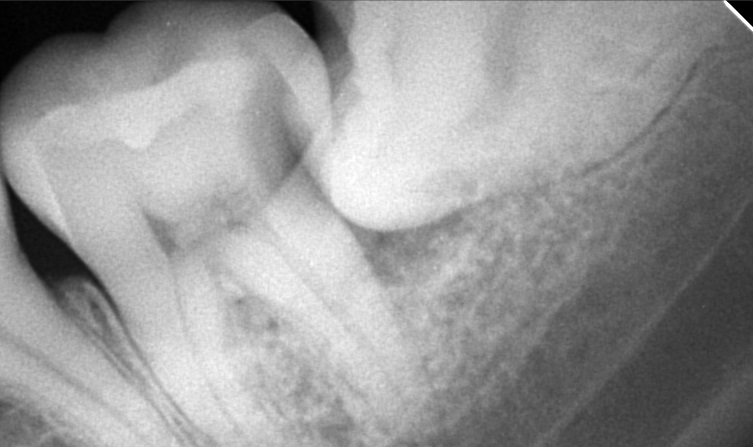

Edit Record Check our patient data records. Add patient information Patient Info Profile picture Last Name First Name Middle Name Birthdate Age Street Barangay City Country Zip Code Contact number Email Procedure 04/02/22 - extraction 37 odontectomy 38 laser hemo 5 sutures- surgeons knot xray 04/09/22 - suture removal/ irrigate/ 5 sutures removed 11/05/24 EXO #18 & #28 11/13/24 Install of Ceramic brace U/L 60,000 dp 10,000 11/29/24 Reattached #35 12/13/24 Adj same wire 01/04/25 Adj same wire new buccal tube Reattached #45 02/07/25 Adj 16 NITI U/L IPR #12/32 03/11/25 Adj reattached #15 04/09/25 16 SS U 18NIti L chain 22-12 IPR-4 front teeth upper 05/16/25 adj w / flouride IPR lateral to lateral #12 L #11 M #21D #22 M for Resto 06/-7/25 IPR #12 M chain 4 ant. U reattached #22 07/09/25 18 SS U/L 08/02/25 same wire 09/20/25 same wire class II elastic rabbit 3.5oz (canine to lower molar) chain canine to canine 11/19/25 adjustment 12/20/25 adjustment rabbit 3.5oz 02/19/26 Adjustment Replace new bracket #45 Rabbit 3.5oz 04/16/26 Adjustment re-attached #45 05/21/26 adjustment re-attached #45 File cabasar3738-3.jpg File 2 cabas3738.jpg File 3 File 4 File 5 File 6 File 7 File 8 File 9 File 10 File 11 File 12 File 13 File 14 File 15 File 16 File 17 File 18 File 19 File 20 Retain Record Retain Record Yes No Save Your Changes